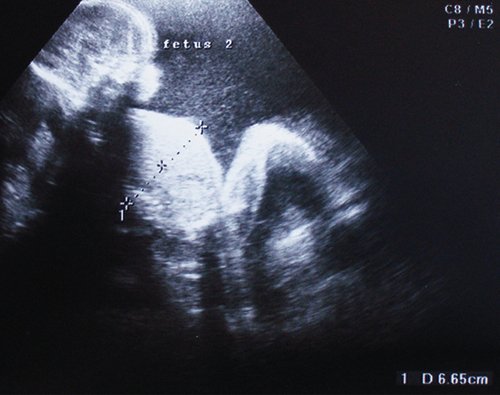

Рис. 2. "Застрявший" близнец ("кокон-признак") - косвенный критерий олигогидрамниона. Плод фиксирован у передней стенки матки, неподвижен. Полигидрамнион близнеца-реципиента (глубокий карман амниотической жидкости ниже изображения плода). Cимметричная задержка роста плода-донора. На сонограмме его мочевой пузырь еще визуализируется. I стадия ФФТС.

Определение выраженного многоводия амниотической полости большего плода не вызывало затруднений и характеризовалось значительной глубиной вертикального кармана амниотической жидкости (11,34±2,26 см). В то же время адекватное измерение размеров амниотической полости меньшего плода оказалось почти невозможным, особенно в случае агидрамниона, так как амниотическая оболочка плотно прилежит к плоду, "укутывая" его. Ультразвуковой симптомом агидрамниона при этом служит признак "кокона", или "застрявшего" плода ("stuck twin"): плоддонор прилежит к одной из стенок матки, фиксирован собственной амниотической оболочкой, неподвижен [3]. Признак сохранялся при динамическом наблюдении на всех стадиях прогрессирующего ФФТС. Формированию агидрамниона патогенетически предшествовало появление прогностически неблагоприятного ультразвукового симптома - отсутствия визуализации мочевого пузыря донора, что свидетельствовало о запуске патологических гемодинамических механизмов, прогрессивном течении синдрома и развитии его II клинической стадии.